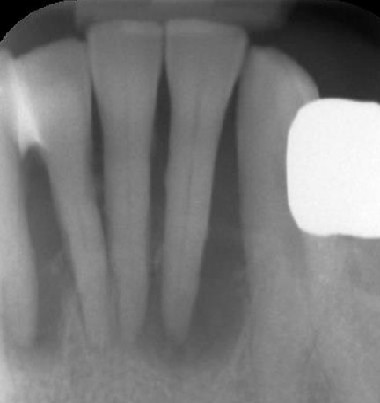

1/15 - X-ray shows a 3-dimensional periondontal defectSoft tissue augmentation and GBR with mucoderm® and maxresorb® - Dr. S. Scherg

X-ray shows a 3-dimensional periondontal defect